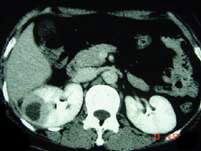

问题 女,12岁,右腰部疼痛10天,尿检可见大量的脓细胞CT平扫+增强如图所示,应诊断为 ( )

选项 A、右侧肾癌 B、右肾结核 C、右侧感染性肾囊肿 D、右肾转移瘤 E、右肾脓肿

答案 E